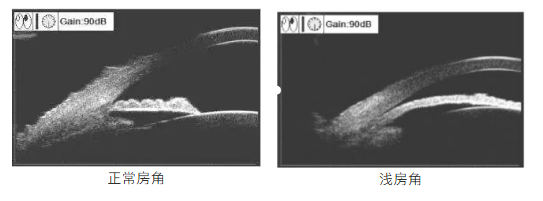

要确诊青光眼,唯一的办法就是去医院做详细的检查。特别是那些有青光眼家族史的人,年龄超过40岁的人,每年都应该做一次检查。如果存有前房浅、眼轴短、晶体厚等情况,更要提高警惕。